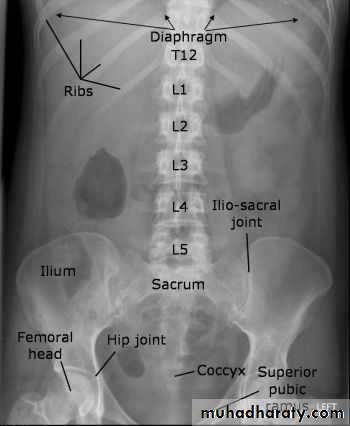

Positioning

• Supine AP

• Erect AP

• Lateral decubitus

The main purpose of horizontal beam films is to detect air-fluid levels and free intraperitoneal air

RADIOGRAPHIC ANATOMY